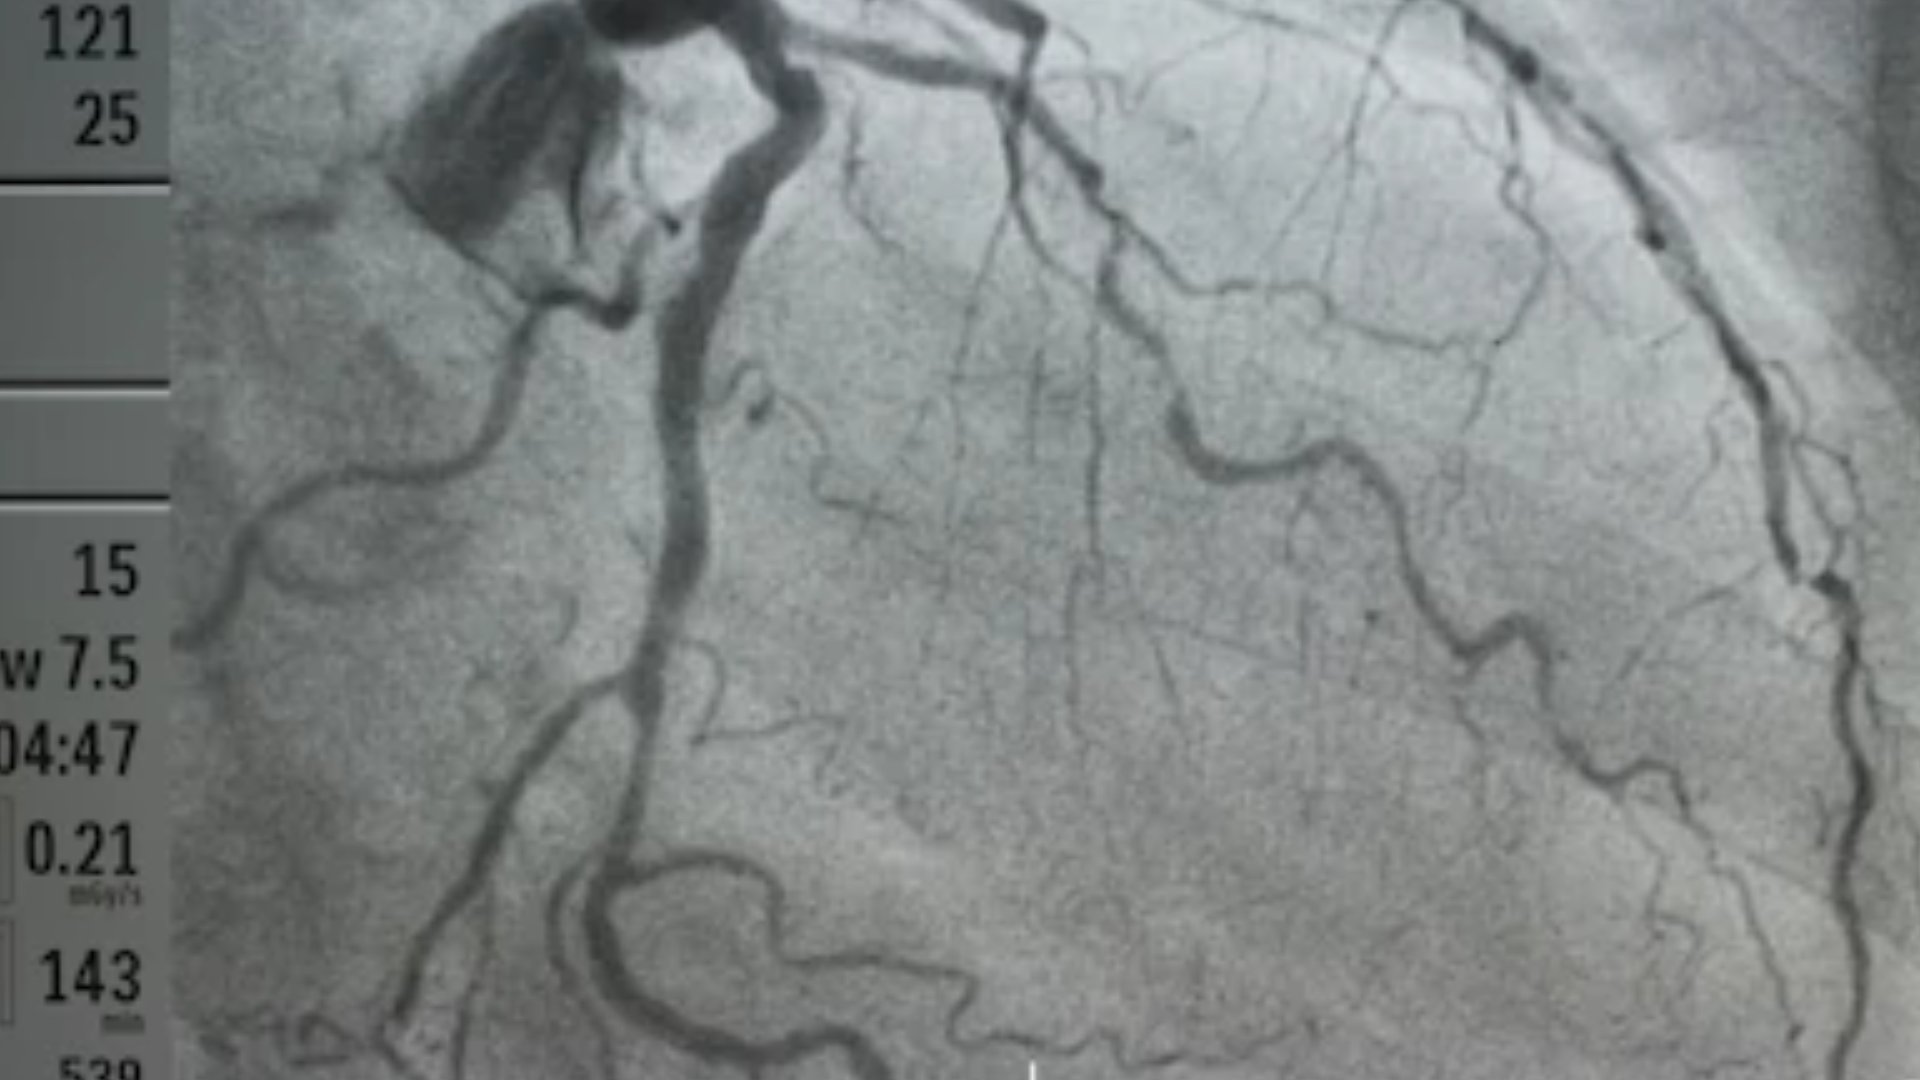

এনজিওগ্রাফি হলো এমন একটি প্রতিবিম্ব তৈরির পরীক্ষা যেখানে শরীরের রক্তনালিকা সমূহ দেখার জন্য এক্স-রে ব্যবহার করা হয়।

এই পরীক্ষার মাধ্যমে রক্তবাহী শিরা বা ধমনি গুলো সরু, ব্লক বা প্রসারিত হয়েছে কিনা তা নির্ণয় করা যায়। রক্তনালীতে ব্লক এবং ররক্তনালি সরু এবং অপ্রসস্ত হলে শরীরের রক্তের স্বাভাবিক প্রবাহ বিঘ্নিত হয়।

এই পদ্ধতি সম্পন্ন করার সময় চিকিৎসক রোগীর দেহে একটি তরল পদার্থ একটি সরু এবং নমনীয় নলের মধ্য দিয়ে প্রবেশ করিয়ে দেন।

নলটিকে ক্যাথেটার এবং তরল পদার্থটিকে ডাই বলে। এই ডাই ব্যবহার এর ফলে রক্তনালী গুলো এক্সরের সাহায্যে দৃশ্যমান হয়।